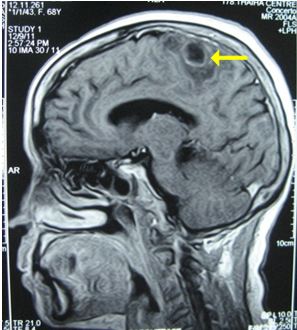

Chụp MRI sọ não (12/12/2011):

Hình 2: Hình ảnh chụp MRI sọ não có khối u não vùng đỉnh trái, 20×19mm, ngấm thuốc quanh u

Chụp MRI sọ não: Sau xạ phẫu 6 tháng bằng dao gamma quay: khối u não tan biến hoàn toàn

Trước điều trị: u não 20×19mm

Sau điều trị 6 tháng: u tan hoàn toàn